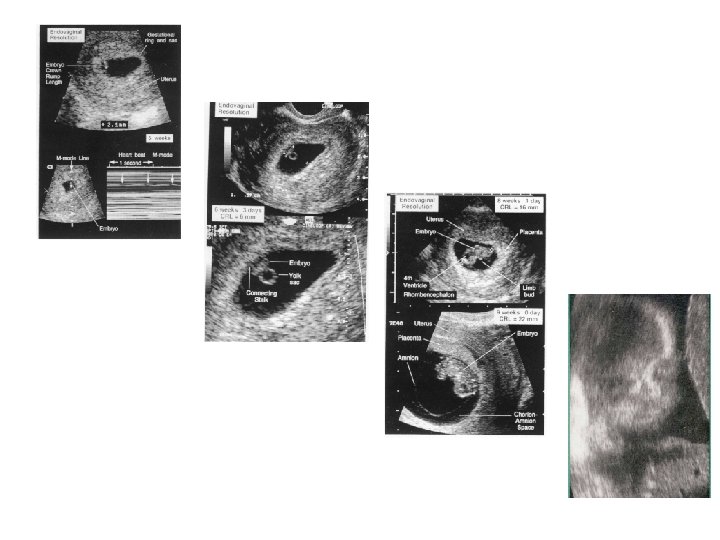

Ultrasound in early pregnancy (before 12 weeks ) - Dating Scan Dating ultrasound A 'dating ultrasound' or 'dating scan' is a scan done early in pregnancy (before 12 weeks ) . It is usually done to check how many weeks pregnant you are and therefore to calculate the estimated due date, but it can be done for other reasons . Only a few women need a dating scan .

We always recommend mums get a definitive dating scan closer to 12 weeks as this will be much more accurate ." . WoW babies confirms that it's worth the wait for the 12 week scan . "Definitely agree that dates from early scans are not accurate . Just half a millimetre at such an early stage can change your date by a week .

During the 16-week scan , you can expect to see a baby that is fully formed but just very small . But, if their development is on track, you should still be able to see arms, legs, fingers, toes . . .